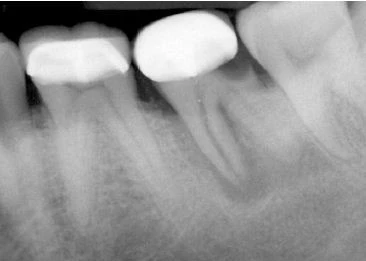

Hình 16. Khi có khoảng trống giữa chất trám bít ống tuỷ và thành ống tuỷ thì nghi ngờ cao có chia chân răng.